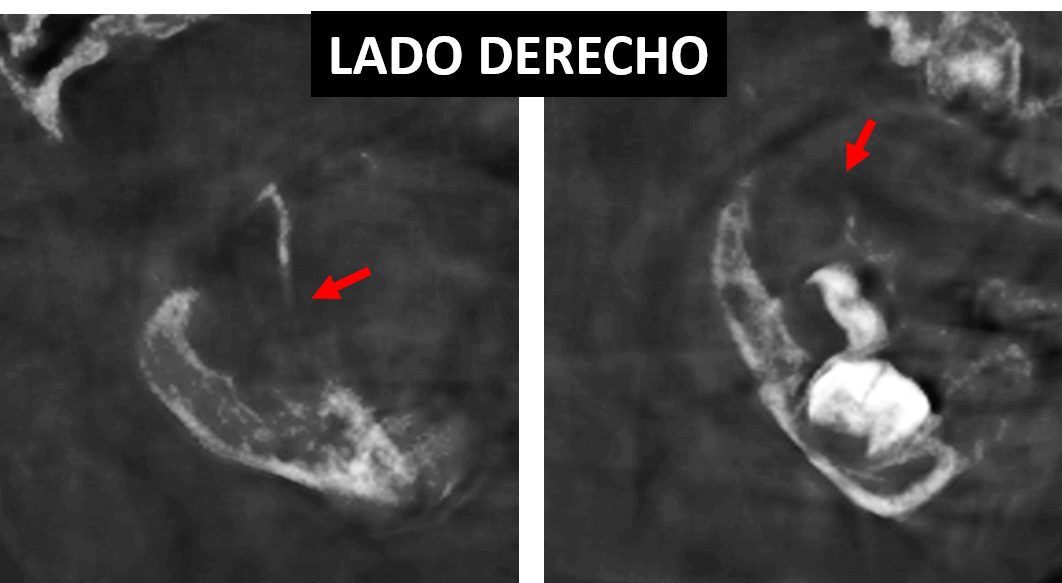

Fig.6

En las imágenes tridimensionales (Fig.6) se observa los signos tomográficos anteriormente descritos en ambos lados del maxilar inferior. Se consideran signos tomográficos de una lesión de aparente naturaleza tumoral.